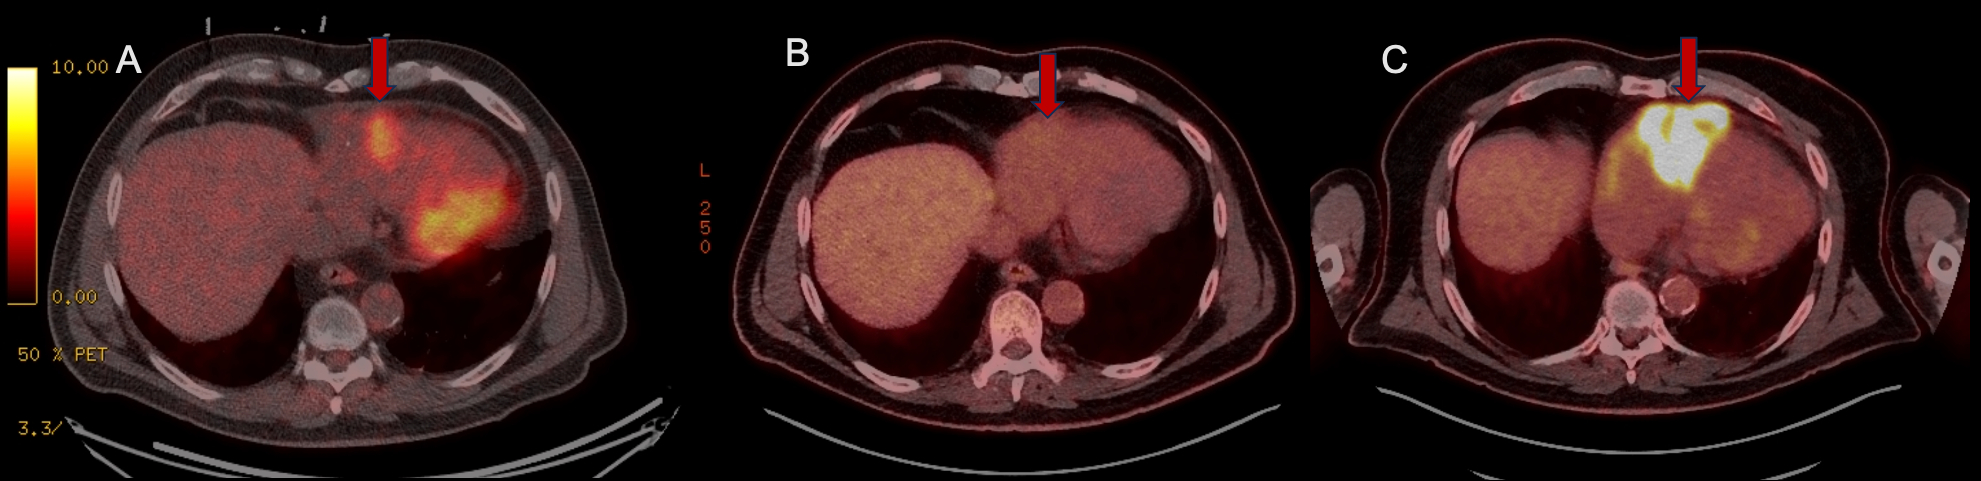

Abstract Body (Do not enter title and authors here): A 65-year-old male with history of coronary artery disease with percutaneous coronary intervention six months earlier presented with one month of fevers, night sweats, chest pain, muscle aches, fatigue, dyspnea on exertion and palpitations. CT chest revealed a 9x5cm mass in the right atrium and right ventricle, which was confirmed on TTE. He had a TTE two weeks earlier without evidence of a mass. Cardiac MRI further revealed a large pericardial effusion and the cardiac mass encasing the right coronary artery and superior vena cava causing near occlusion of the distal SVC. A biopsy and pericardiocentesis revealed acute leukemia of ambiguous lineage, but bone marrow biopsy and serial lumbar punctures were negative for disease. The patient underwent treatment with intravenous and intrathecal chemotherapy. His course was complicated by atrial fibrillation with rapid ventricular response requiring a rate control strategy as his chemotherapy-induced thrombocytopenia prevented anticoagulation. Initial restaging scans one to three months after chemotherapy showed resolution of uptake and reduction in mass size. However, subsequent scans one month after prior scans showed the mass to have increased uptake and size, so partial resection was performed with repeat pathology confirming acute leukemia of ambiguous lineage. Initial plans for bone marrow transplant were placed on hold given local recurrence. Currently, he is receiving palliative radiation as a bridge with hope for more targeted therapy.